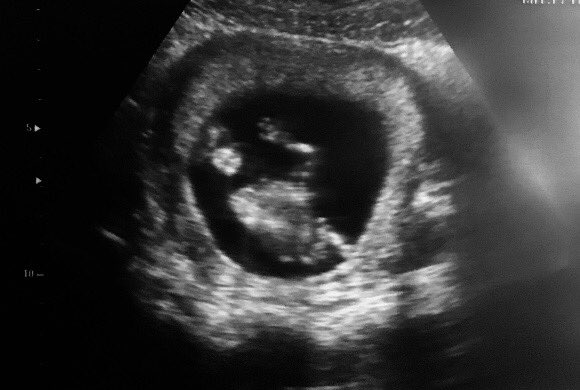

My son sent me this sonogram pic for Christmas. This will be my first grandbaby—a Boy. This sonogram was done at just 12 weeks. My son said they couldn’t see the baby & asked the dr where the baby was & the baby threw his hand up & waved at that very moment. Pretty amazing💕